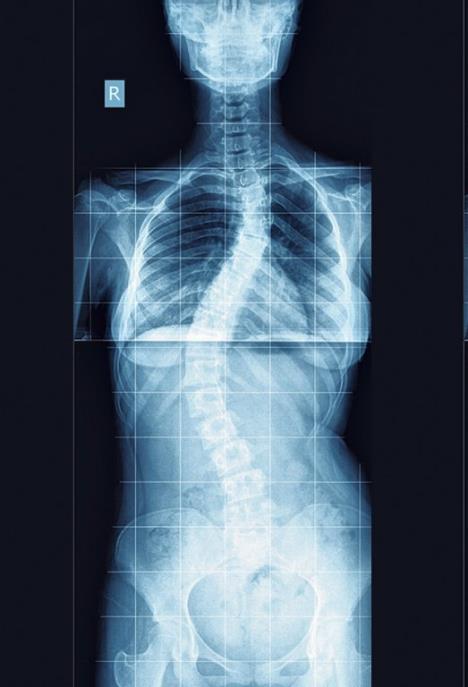

Primetili ste da vaše dete neobično stoji i korača, što vas prilično zabrinjava jer, kako vam se čini, nije tako izgledalo do pre samo mesec dana. Da stvar bude strašnija, uočavate i da ono pomalo krivi gornji deo tela u stranu, čak mu je i jedno rame spuštenije od drugog. Iako ne bi trebalo da paničite, treba da znate da takve promene na muskulaturi deteta nisu zanemarljive, pa bi trebalo da se obratite lekaru. Znaci za alarm su i previše uspravno držanje tela, pri čemu je stomak značajno izbačen. Stručnjaci ističu da su to pojavni oblici najčešćih i najočiglednijih deformiteta kičmenog stuba - kifoza, skolioza i lordoza.

- Kriva kičma kod dece nastaje na nekoliko načina. Najčešći oblik tog problema je skolioza, koja nastaje usled naslednih faktora, ali gde faktori okoline imaju presudnu ulogu u razvoju deformiteta. Drugi način nastanka poremećaja na kičmi može biti usled urođene anomalije pršljenova, a reč je o urođenoj kongenitalnoj skoliozi. Postoji još vrsta skolioza koje nastaju usled raznih metaboličkih poremećaja i neuromišićnih oboljenja - istakao je za Dr Kurir mr sc. med. dr Stanko Miličković i naglasio da je veoma važno da roditelji slušaju savete lekara i usmere svoje dete na pravu terapiju.

Inače, treba imati u vidu da mnoga deca često samo „pate“ i od nepravilnog držanja. Ono se može razlikovati od deformiteta po tome što je mališan u stanju da se potpuno ispravi iz nepravilnog položaja, a da mu pritom i kičma bude prava. I loše držanje je neophodno korigovati na vreme da ne bi došlo do ozbiljnih i trajnih promena na koštano-mišićnom sistemu. Deformiteti kičmenog stuba nisu uvek prepoznatljivi, a ponekad i lekar specijalista ima dilemu i upućuje dete na rendgensko snimanje da bi utvrdio dijagnozu.